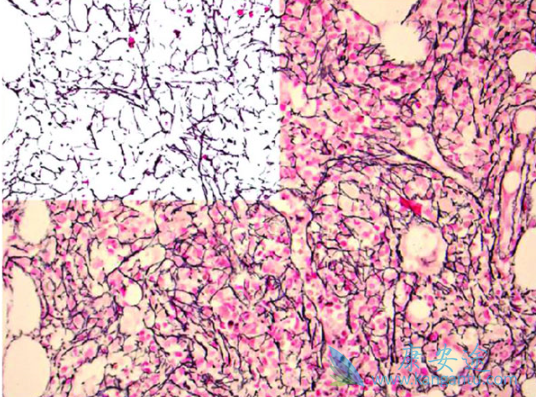

2019年8月16日,FDA批准Inrebic (fedratinib)胶囊用于中危-2或高危骨髓纤维化成人患者。骨髓纤维化是一种罕见的骨髓疾病,患者可能出现以下症状:极度疲乏、气短、肋下疼痛、发热、盗汗、瘙痒和骨痛。在此之前,只有Jakafi(鲁索替尼)于2011年获批用于骨髓纤维化患者。

FDA根据一项纳入了289名骨髓纤维化患者的临床试验结果批准Inrebic上市。试验将患者随机分为三组:安慰剂, Inrebic口服400 mg/d,Inrebic 口服500 mg/d。结果表明,采用Inrebic 400 mg/d 的96名患者中的35位疗效显著,第6个疗程结束时(24周),患者脾脏的体积缩小了35%甚至更多,接受Inrebic治疗的患者中,有36名患者骨髓纤维化相关症状减少至少50%,相关症状指盗汗、瘙痒、腹部不适、容易产生饱腹感、左侧肋下疼痛、骨或肌肉痛等。